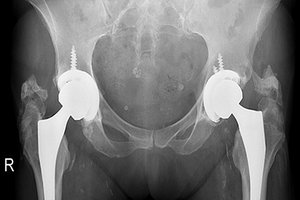

Figure 1 is an X-ray taken to evaluate the status of the hip replacements. The film demonstrates heterotopic ossification involving both hips. There is atherosclerotic calcific plaquing in the femoral arteries, and other calcifications in the pelvic basin including phleboliths, calcific plaquing in the iliac arteries, mesenteric lymph node calcification and/or uterine fibroid.

There is a problem with this AP view. The end of the stem of the femoral component of the THA is not visualized on either side. What should be done is either take an AP hip of each hip to assess the position of the stem or take the same view, but position the focal spot lower down to include the stems. The distal femoral component needs to be visualized to rule out possible loosening.

FIG 1 78 y/o female with right hip total hip arthroplasty two years prior (left THA done four years before the right).

Are we going to treat this 78-year-old patient with bilateral THA? Will she gain any benefit from our treatment? What grade does she present with per the Brooker classification? I'm confident about grading the right hip, but not quite certain about the left. I would need to evaluate clinical findings, including range of motion; and obtain images of the total hip prosthesis to rule out mechanical loosening. A bone scan would determine if heterotopic bone growth is still active.